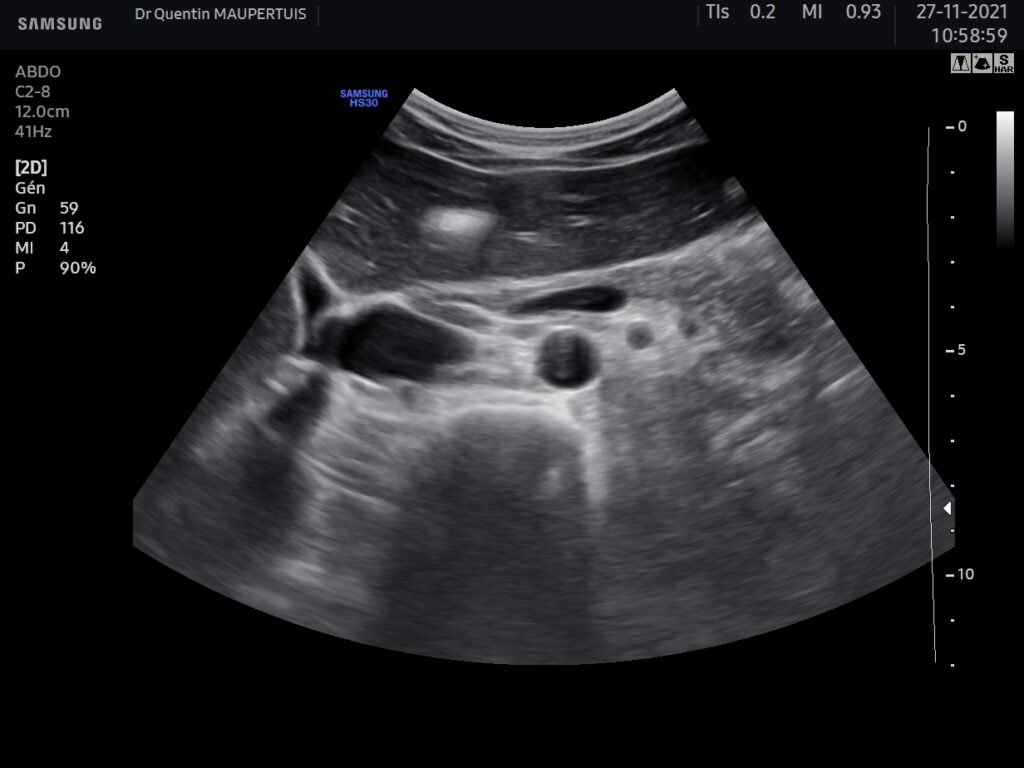

Sur les coupes de droites on identifie à coup sur le pancréas grâce à l’aspect caractéristique du confluent spléno-mésaraïque (CSM) et aux vaisseaux sous jacents : La VCI en arrière de la tête du pancréas, naissance de laveine rénale gauche (VRG) qui passe dans la pince Aorto(Ao)-mésentérique(AMS), lui donnant cette aspect dilaté en amont.